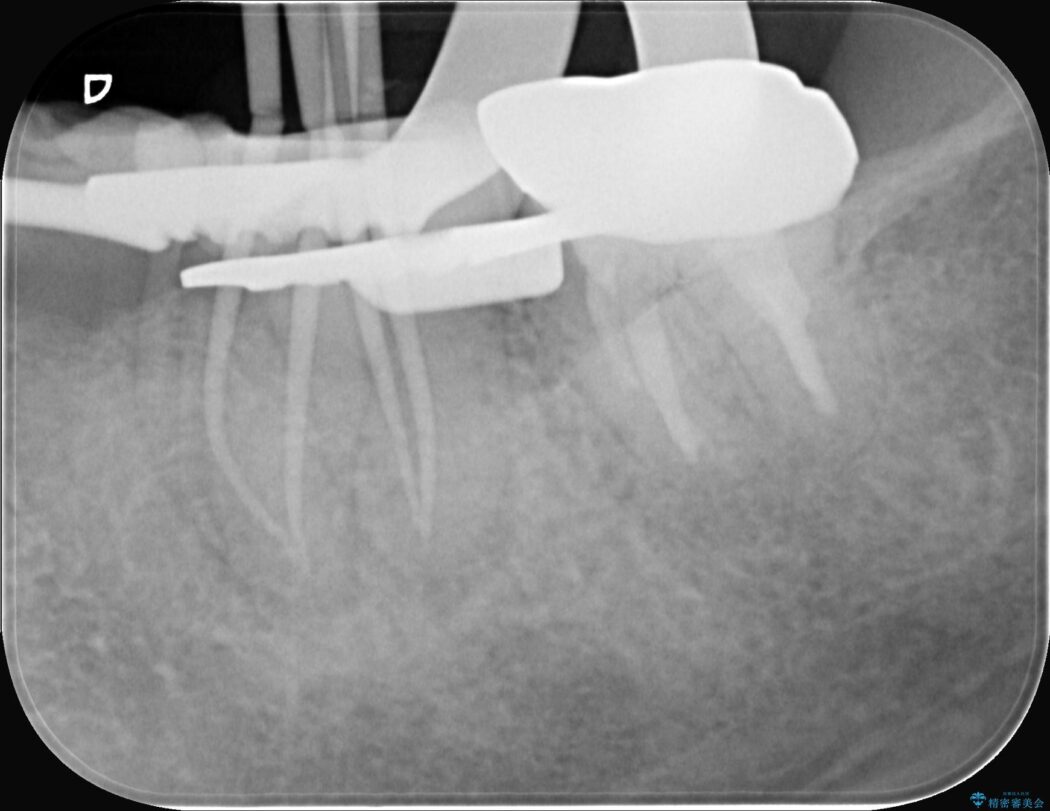

まず、治療中の細菌感染を防ぐためにラバーダムを使用。次に、歯科用顕微鏡で治療部位を何十倍にも拡大しながら、狭窄した根管の入り口を探し、慎重に拡大・清掃を行いました。顕微鏡を用いることで、肉眼では不可能だった根管内部の細かい構造を確認しながら、感染源を徹底的に除去することができました。これにより、難症例の奥歯でも再発リスクを抑えた適切な処置を行うことができ、治療後に痛みは解消。大切な歯を長期間にわたり保存することができました。